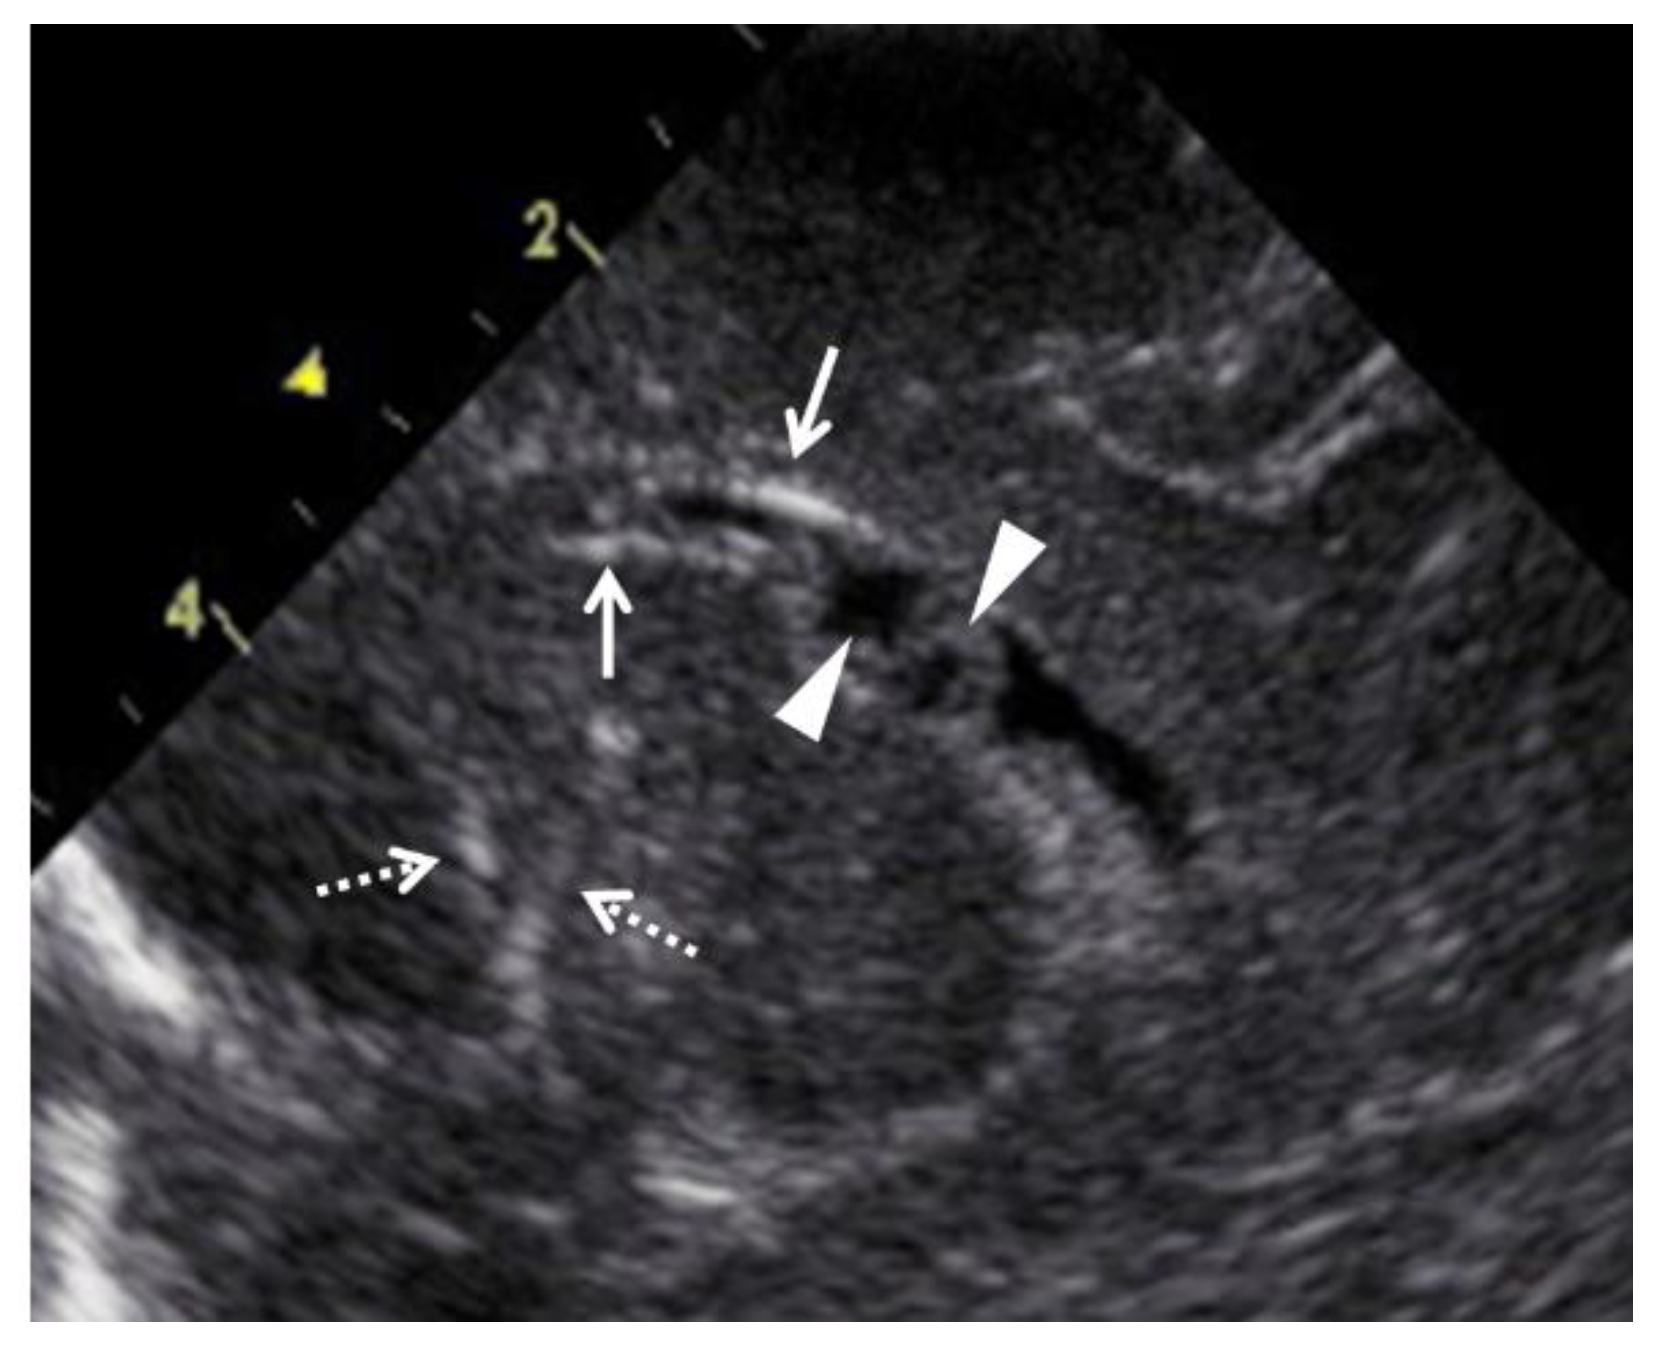

All 18 newborns, including 2 cases of early neonatal death, underwent physical and imaging examinations conducted by experienced neonatologists, as well as blood tests, as early as possible after birth. For the 16 live newborns, cCMV was confirmed by a urine CMV-DNA PCR analysis. The definition of ventriculomegaly used for the newborns was the same as that for the fetuses. Microcephaly was defined as an HC ≤ the mean −2.0 SD for newborns of the same age and sex. Intracranial calcification and pseudo cysts in the brain were detected by ultrasounds (Figure 3). Hepatomegaly was defined as, on palpation, a liver edge ≥ 3.5 cm below the right costal margin. Splenomegaly was defined as, on palpation, a tip of the spleen ≥ 2.0 cm below the left costal margin. Furthermore, the 16 live infants underwent physical and auditory brain-stem response examinations every 3 months until 1 year of adjusted age and every 3–12 months thereafter. The neurological outcomes at 1.5 and 3 years of adjusted age were assessed using physical examinations and the developmental quotient (DQ) using the Kyoto Scale of Psychological Development [26]. Mild and severe developmental delays were defined as overall DQ scores of 70–79 and <70, respectively.

Figure 3. Abnormal ultrasound findings in the brain of newborns with congenital cytomegalovirus infection. Arrows indicate periventricular calcification, and arrowheads indicate pseudocysts in the cerebral ventricle. Dashed arrows indicate lenticulostriate vasculopathy.